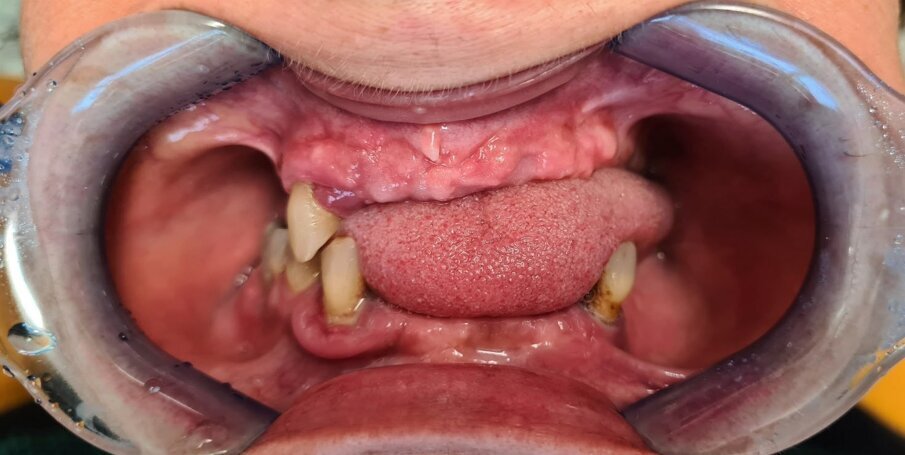

Paziente donna di ottant’anni, presenta uno stato di salute ottimale, non assume farmaci. Dal punto di vista odontoiatrico chiede una riabilitazione delle due arcate con dei denti fissi perché le attuali protesi removibili con ganci le stanno creando ormai da troppi anni un grande disagio. Come dalla ortopantomografia possiamo evidenziare uno stato ormai precario degli elementi rimasti (Figg. 1-3).

Fig. 1_Caso iniziale senza protesi.